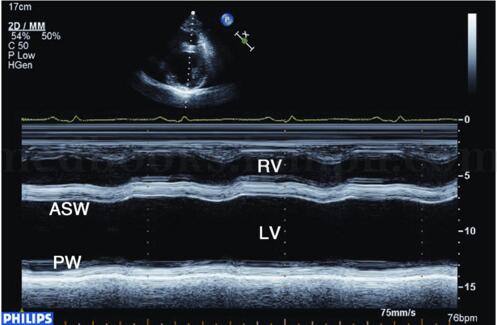

图2‐1‐180 M型超声显示左室后壁明显变薄,运动明显减弱甚至消失,前壁运动亦减弱

二维超声表现为左室显著扩大,几何形变,可呈球形扩张(见图2‐1‐179),左室心肌节段变薄,回声明显增强,运动明显减弱或消失,室壁增厚率消失,并伴有左室壁普遍运动减弱和不协调,左室泵血功能明显减低(见图2‐1‐180),二尖瓣开放幅度减低。左室腔内血流速度常较缓慢,有时可见附壁血栓形成。